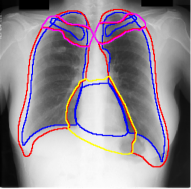

For each of these three datasets, we use three noise settings, denoted by , and . and are two settings synthesized by our Markov process with (expansion) and (shrinkage), respectively. Figure 4 shows examples of our synthesized label noise. We also include the mix of random dilation and erosion noise used by previous work (Zhu et al., 2019; Zhang et al., 2020b; a). This is achieved by randomly dilate or erode a mask with a number of pixels. Note that our Markov label noise can theoretically include this type of noise by setting . Detailed parameters for these settings are provided in the Appendix.

Real-world label noise. To evaluate with real-world label noise is challenging. We are not aware of any public medical image segmentation dataset that has both true labels and noisy labels from human annotators. Therefore, we use a multi-annotator dataset, LIDC-IDRI dataset (Armato III et al., 2015; Armato et al., 2011; Clark et al., 2013), and the coarse segmentation in a vision dataset, Cityscapes (Cordts et al., 2016). The LIDC-IDRI dataset consists of 1018 3D thorax CT scans where four radiologists have annotated multiple lung nodules in each scan. The dataset was annotated by 12 radiologists, and it is not possible to match an annotation to an expert. We use the majority voting as the true labels and the union of four annotations as noisy labels. We process and split the data exactly the same way as Kohl et al. (2018). Cityscapes dataset contains 5000 finely annotated images along with a coarse segmentation by human annotators that we use as the “noisy label”. We only focus on the ‘car’ class because (1) cars are popular objects and are frequently included in images; (2) the coarse annotation of cars is very similar to noisy annotation in medical imaging – they are reasonable distortions of the clean label without changing the topology. See Figure 4(c) for an example. The detailed settings of LIDC-IDRI and Cityscapes can be found in Appendix A.2.1.

Table 1 shows the segmentation results of different methods with synthetic noisy label settings on JSRT , ISIC 2017 and Brats 2020 dataset. Note that QAM cannot be applied to Brats 2020 dataset because their network is designed for 2D only. We compare DICE score (DSC) on testing sets (against the clean labels). For each setting, we train 5 different models, and report the mean DSC and standard deviation. In and , where biases show up in noisy labels, the proposed method outperforms the baselines by a big leap in total case. The compared methods, however, only work when little bias is included, like . is equivalent to setting in our Markov model, resulting in . We also test the proposed method on real-world label noise, results shows in Table 2. Figure 5 shows examples of label correction results. We provide more qualitative results in the Appendix A.4.